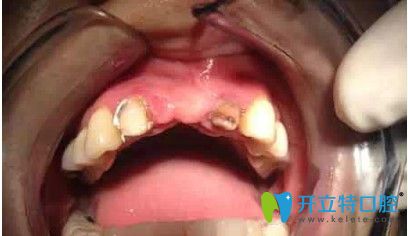

刘女士,33岁,据她描述,自己多年前在国内一家口腔医院做了烤瓷冠,但由于时间长变的松动,考虑到自己还年轻,为了一步到位,她来韩国安特丽做了多颗牙种植。

在拆除烤瓷桥后,发现她的口内埋伏牙,把埋伏牙拔除后,很顺利的植入了种植体,完成了种植牙。